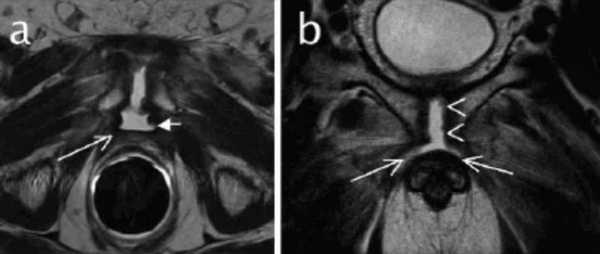

МРТ-признаки остеомиелита лонных костей: расширение сочленения и скопление жидкости с формированием параартикулярных затеков (длинные стрелки), разрастание грануляционной ткани (короткие стрелки), Т2-ВИ, аксиальная (а) и коронарная (в) плоскости